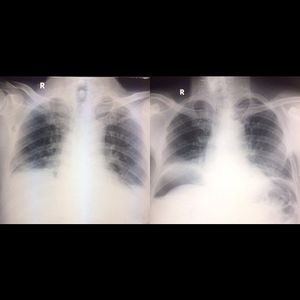

Optimal radiographic technique is important with suspected abdominal perforation. The first photo taken with supine position resulting blunt appereance in both costophrenic recessus which mimicking pleural efusion and there is no free air appereance in sub diaphragma. The second is in same patient buf after 10 minutes in erect position, resulting in large subdiaphragmatic air (outlining the superior surface of the liver). This erect position is very important because at least can detect 2 cc free air which appear as tiny streak air under the diaphragm.